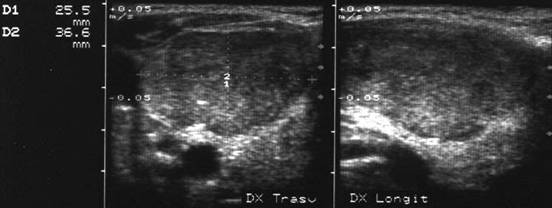

Barbat de 51 ani. Nodul unic in lobul stang, de 25 x 23 x 31mm (9,5 cc), hipoecogen, cu contur net. Citoaspirata: carcinom papilar. Examen histologic: carcinom papilar varianta foliculara

Lob drept, proiectie trasversale si longitudinala.